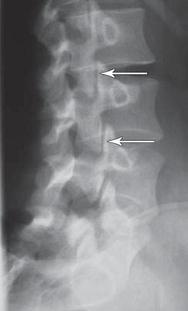

![]() Рентгенограмма № 1. На снимке стрелкой указано расположение дугоотростчатых суставов позвоночника в состоянии нормы Дугоотростчатые суставы осуществляют своеобразный контроль над движениями позвоночника. Например, они позволяют позвоночнику совершать движения, те же сгибание, разгибание, но в то же время ограничивают его движения в горизонтальной плоскости. Последнее позволяет при ротационных движениях позвоночника (от лат. rotatio — «кругообразное движение, вращение»), например при повороте туловища, при наклоне с поворотом, сохранять стабильное сочленение позвоночника и не проворачиваться позвонкам вокруг своей оси. Не меньшим блеском биотехнического совершенства позвонка являются остистый и два поперечных отростка — места прикрепления связок и мышц. Они являются превосходно сконструированными природными рычагами. А что такое рычаг с точки зрения физики? Это твёрдое тело, вращающееся вокруг неподвижной опоры, механизм, позволяющий меньшей силой уравновесить большую. Знаменитый «Великий купальщик» Архимед, который и изложил теорию рычага под действием сил тяжести, сказал по этому поводу: «Дайте мне точку опоры, и я переверну Землю». Почему «Великий купальщик»? Да потому что и до Архимеда люди принимали ванну. Но только лишь он принял её настолько гениально, что до сих пор физики, погружая своё учёное тело в ванну и наблюдая, как поднимается уровень воды, невольно вспоминают закон Архимеда. Так вот, благодаря остистым и поперечным отросткам позвонков, к которым прикреплены мышцы и связки, организм имеет возможность при совершении движений, прилагая малые мышечные усилия, выполнять большую работу. Такие уникальные рычаги просто незаменимы, к примеру, для совершения быстрых и чётких движений, удержания тела в статическом положении и так далее. Связки позвоночника Не последнюю роль в биомеханике позвоночника играют связки (лат. ligamenta — перевязь) — тяжи, пучки, или пластины плотной волокнистой соединительной ткани, опутывающие тела, дуги, отростки позвонков. Они не просто соединяют кости, укрепляют суставы, но и обеспечивают им подвижность. Замечу, что в состав ткани связок входят коллагеновые волокна (коллаген — волокнистый белок; от гр. kolla означающее клей, genos — рождающий, род, происхождение), обеспечивающие прочность связок, и эластические волокна (от греческого elastikos — упругий, гибкий, растяжимый). Благодаря связкам и межпозвонковым дискам отдельные позвонки соединены между собой и представляют собой единую функциональную систему. ![]() Рисунок № 16. Соединения позвонков (поясничный отдел, вид слева). Два верхних позвонка сагиттально распилены В первую очередь хочу упомянуть о трёх уникальнейших связках позвоночника. Это передняя, задняя продольные связки и надостистая связка, которые относятся к группе длинных связок позвоночного столба. Они вызывают определённое восхищение, благодаря своим стабилизирующим функциям. Пожалуй, для того чтобы вы лучше поняли, как гениально природа-матушка позаботилась о нашем позвоночнике, вначале приведу несколько отдалённый, но всё же схожий пример из области инженерных проектов. Вы, наверное, слышали о знаменитой Останкинской телебашне, находящейся в Москве, — одном из выдающихся архитектурных строений XX века. Чем же она привлекательна помимо своей высоты? Своей необычной конструкцией. Когда рождался этот проект, то была поставлена следующая задача: с одной стороны, ствол башни при высоте 533,3 м нужно было сделать стойким, гибким и упругим, и в то же время учесть оптимальное отклонение вершины под действием ветра. С другой стороны, нужно было придумать крепкое и надёжное основание для ствола. Как правило, обычно для высотного сооружения строится фундамент глубокого заложения, служащий в качестве противовеса наземной части любого сооружения. Неожиданный проект в отношении Останкинской телебашни предложил учёный в области строительных конструкций Николай Васильевич Никитин. На инженерную мысль его вдохновил цветок лилии: в стебле он увидел ствол башни, а в лепестках, перевёрнутых вниз, — её опору. Инженерная задача решалась за счёт натянутых сверху донизу, как струны, стальных канатов (в количестве 150 штук, растянутых с силой в 70 тонн), расположенных внутри по окружности ствола башни. Они прочно стягивали конус основания и вырастающий из него «стебель» башни. Так вот, сбалансированное натяжение канатов намертво сцепляло с землёй опоры и удерживало мощный бетонный ствол. Благодаря включению в инженерный расчёт канатов, это так организовало работу опор и связало в единую систему всю конструкцию сооружения, что башня, не имеющая обычного глубокого подземного фундамента, до сих пор выдерживает серьёзные внешние нагрузки, в том числе и сильнейший ветер. Хотя я уверен, что если бы в своё время Николай Никитин обратил внимание на совершеннейшую конструкцию позвоночника, то в своей профессиональной области он, как учёный, сделал бы гораздо более гениальные открытия. ![]() Рисунок № 17. Опора и ствол Останкинской телебашни, находящейся в Москве После того как мы ознакомились с ролью подобных канатов в архитектурных монолитных сооружениях, заглянем в изящный, с ювелирной точностью отмоделированный мир более сложной организации — живой материи, в частности, в мир строения позвоночника — инженерного идеала конструктивных, высокоточных расчётов. Итак, вернёмся к нашим непревзойдённым позвоночным «канатам» — длинным связкам позвоночника: передней, задней продольным связкам и над-остистой связке. К ним вполне применима древняя мудрость: «Истина в простоте». Итак, передняя продольная связка относиться к группе длинных связок позвоночного столба. Это довольно широкий соединительнотканный тяж, который проходит по передней и отчасти по боковым поверхностям тел позвонков и межпозвонковых дисков на всём протяжении позвоночника от нижней поверхности тела затылочной кости, глоточного бугорка и переднего бугорка атланта до первого крестцового позвонка. В верхних отделах связка уже, книзу расширяется. Она тесно прилегает к передней поверхности тел позвонков, прочно фиксирована к надкостнице позвонков и рыхло связана с передней поверхностью межпозвонковых дисков. Это довольно прочное образование, выдерживающее разрыв до 500 кг. Замечу, что при самых тяжких повреждениях позвоночника данная связка почти никогда не рвётся поперечно, а лишь разволокняется продольно. Многие авторы, описывая её назначение, считают, что предназначена она всего лишь для ограничения разгибания позвоночника при движении его кзади. (Читая подобное чуть ли не в каждой книге, невольно с юмором вспоминаешь «закон Вейнера о библиотеках», в котором говорится, что «в библиотеках ты не найдёшь ответов, а только отсылки».) Однако на самом деле, на практике, роль передней продольной связки более значима, чем принято считать. Она участвует в регулировке внутридискового давления. Да и вообще скрывает в себе ещё много познавательного материала для науки. Это уникальная связка, которая требует более тщательного изучения её функций, в том числе со стороны физиков. |